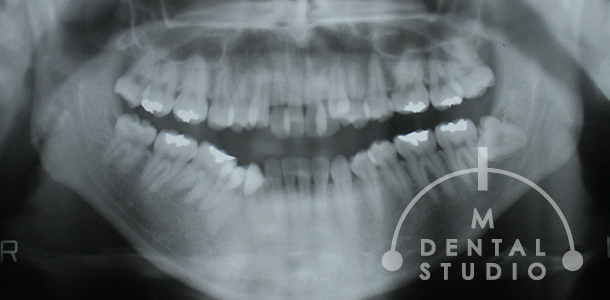

レントゲン写真(術前)

矯正治療・術前のレントゲンです。レントゲン上でも、歯列が波打っています。また、親知らずも全て存在しています。

この矯正治療・終盤時点のレントゲンです。既にこの時点では便宜抜歯3本と上の親知らず2本抜歯を行っています。しかし、下アゴの親知らずを抜いていません。このケースのように、『下の親知らずがあるから』矯正必ずできない訳ではございません。

※親知らずは、患者様の状況に応じて抜くことを協議します。

※また当院では親知らずを抜かないで矯正する場合がございます。必ず抜くとも限りません。